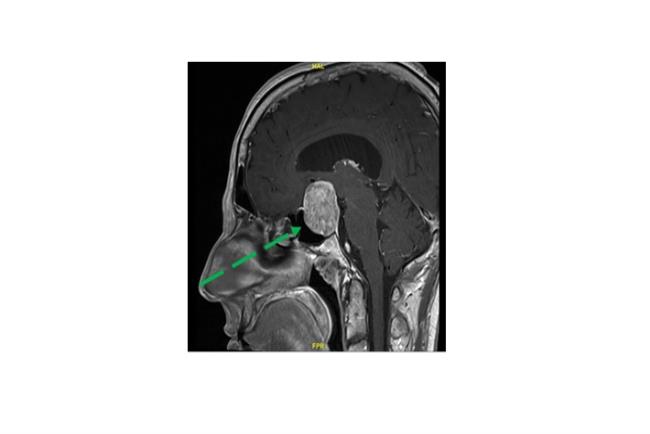

הצלחת הניתוחים האנדוסקופיים של ההיפופיזה הובילה בעשור האחרון ליכולת לבצע ניתוחים לכריתת גידולי בסיס גולגולת מסוגים שונים כגון מנינגיומות, קרניופרינגיומות וכורדומותבגישה אנדוסקופית מתקדמת לבסיס הגולגולת. באמצעות שימוש בגישה זו ניתן למנוע את הצורך בביצוע של הליכים כירורגיים מורכבים המערבים פתיחה נרחבת של הגולגולת ובשל כך גם מצריכים אשפוז ממושך. בדומה לניתוחים אנדוסקופים טרנס ספנוידלים לכריתת גידולים בבלוטת יותרת המוח, ניתוחי המוח המבוצעים בגישה אנדוסקופית מתקדמת לבסיס הגולגולת מאפשרת גישה ישירה לאזור הגידול מבלי לפגום ברקמת המוח. תוצאותיהם של הליכים אלה לרוב טובים יותר, ללא צורך בביצוע חתכים נרחבים בקרקפת או פתיחה נרחבת של הגולגולת , ומצריכים זמן אשפוז קצר יותר.

מנינגיומה של בסיס הגולגולת הקידמי (טוברקולום סלה) באישה בת 55 אשר סבלה שנים רבות מכאבי ראש. נותחה בגישה אנדוסקופית (דרך האף) לכריתה מלאה של הגידול